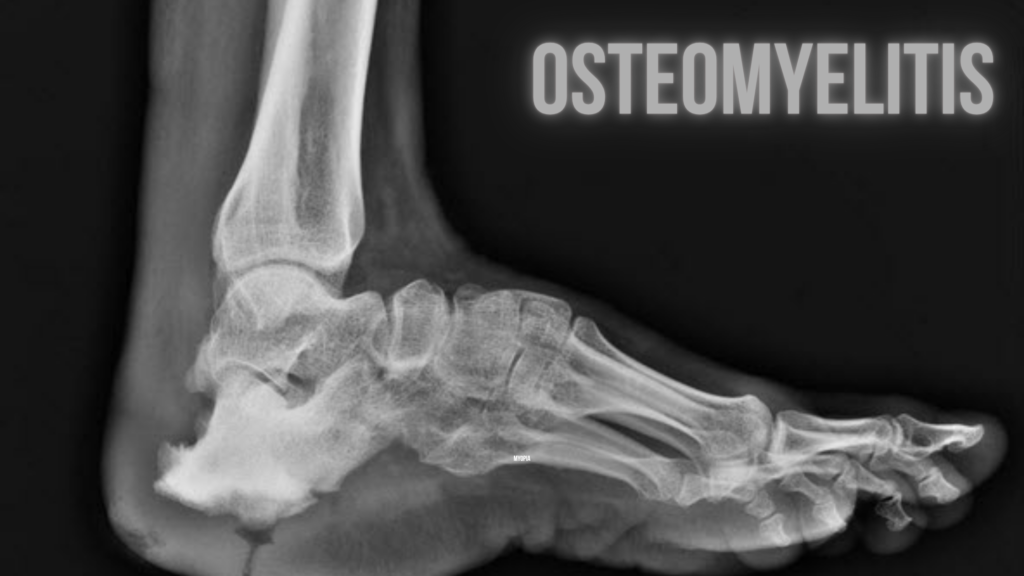

Osteomyelitis

🦴 Osteomyelitis Osteomyelitis is a serious infection of the bone, typically caused by bacteria (most commonly Staphylococcus aureus), and less often by fungi or other organisms. It can affect people of any age and can become chronic if not treated promptly. 🧬 Causes Osteomyelitis can occur through: ⚠️ Risk Factors 🧪 Symptoms 🔬 Diagnosis 💊 […]